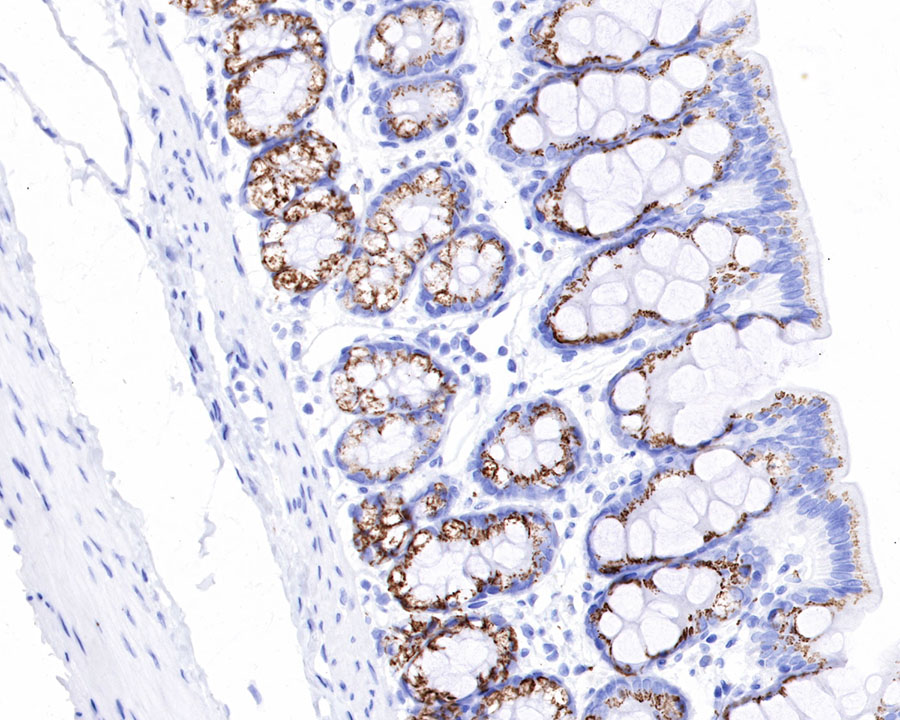

IHC shows positive staining in paraffin-embedded rat colon. Anti-GP73/GOLPH2 antibody was used at 1/1000 dilution, followed by a HRP Polymer for Mouse & Rabbit IgG (ready to use). Counterstained with hematoxylin. Heat mediated antigen retrieval with Tris/EDTA buffer pH9.0 was performed before commencing with IHC staining protocol.